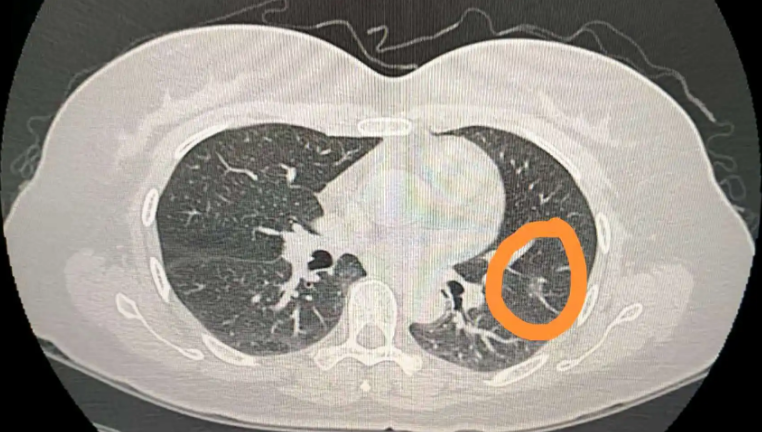

肺部出现6mm磨玻璃结节的原因有很多,可能是肺部炎症、过敏、肺结核或肺部肿瘤引起的。需要及时就诊,了解具体情况再来对症治疗。不要盲目用药,以免加重症状或掩盖病情。

4.肺部肿瘤:部分患者有肺部肿瘤疾病。由于肿瘤细胞所在的肺组织形成的结节密度高于正常肺组织,可能导致肺部出现6mm的磨玻璃结节,需要及时进行针对性治疗。早期手术切除可以判断疾病的良恶性程度。如果是恶性肺透明结节,应及时进行放化疗或靶向药物治疗。